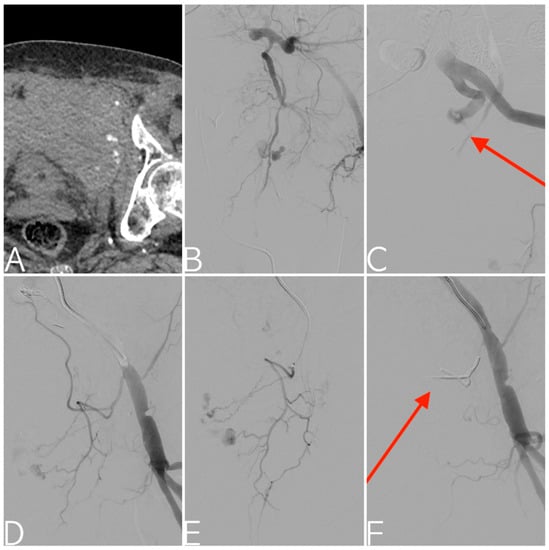

2.2. Treatment